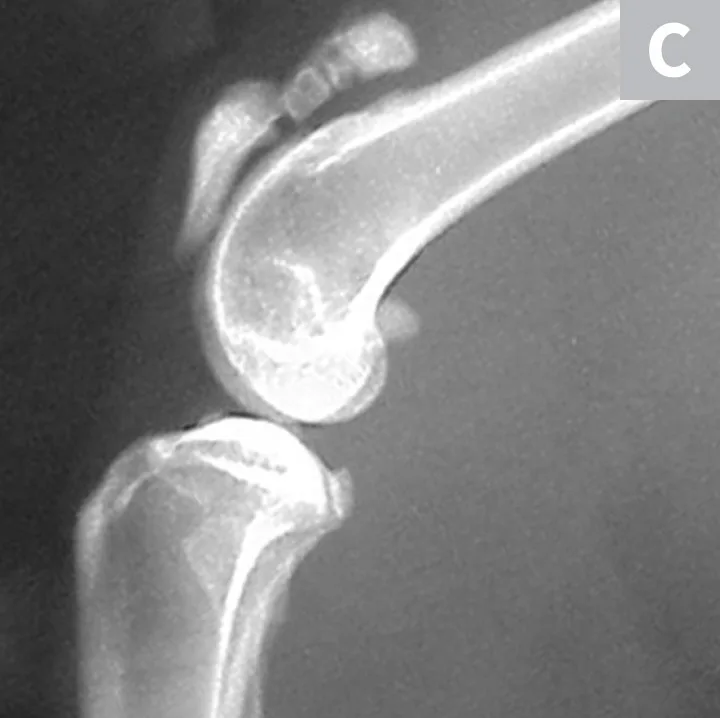

The patient received buprenorphine (15 µg/kg IV) for analgesia, followed by an induction with alfaxalone (0.5 mg/kg IV) and general anesthesia with isoflurane to facilitate dental and orthopedic radiography. Dental radiographs revealed persistent deciduous teeth and impacted permanent teeth. Lateral and craniocaudal pelvic limb radiographs revealed a displaced left patellar fracture and a nondisplaced right patellar fracture (Figure 2).

Lateral radiographs of the left (A) and right (B) stifles show a complete, displaced left patellar fracture and a nondisplaced right patellar fracture, respectively.